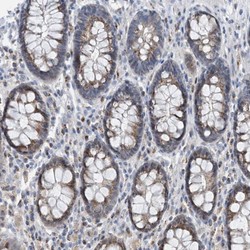

- Main image

- Experimental details

- Immunohistochemical staining of human rectum shows moderate cytoplasmic positivity, with a granular pattern in glandular cells.